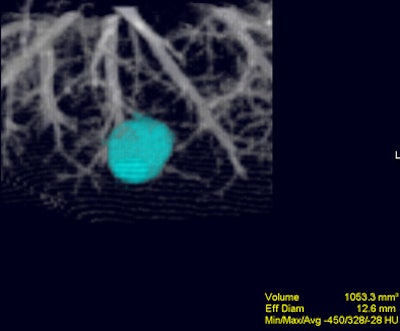

![]() |

| Volume-rendered image obtained with Vitrea 2 program shows a segmented nodule with volumetric measurement results. Image courtesy of Dr. Jin Goo. |